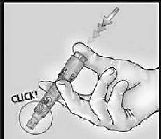

4-İŞARET PARMAĞINI KULLANARAK ENJEKTE EDİN

Mikro-iğnenin saplanmasıyla birlikte deri yüzeyinde hafif bir baskı uygulamaya devam edin ve pistonu itmek üzere işaret parmağını kullanarak aşıyı enjekte edin.

Bu işlem sırasında damar testine gerek yoktur.

5-PİSTONU SIKICA İTEREK İĞNE MUHAFAZASINI HAREKETE GEÇİRİN

İğneyi deriden çıkartın.

İğneyi kendinizden ve diğerlerinden uzak duracak şekilde tutun. Aynı elin baş parmağını kullanarak pistonu çok sıkı bir şekilde iterek iğne muhafazasını harekete geçirin.

Bir klik sesiyle birlikte iğneyi kaplamak üzere iğne muhafazası dışarı çıkacaktır.

Sistemi derhal en yakınınızdaki uygun tıbbi atık kutusuna atın. Enjeksiyon sonrasında bir püstülün varlığı gözlemlensin veya gözlemlenmesin, gerçekleştirilen enjeksiyon başarılı sayılır. Aşı uygulamasının ardından, enjeksiyon yerinden bir miktar aşı içeriğinin vücut dışına sızması, aşının tekrar uygulanmasını gerektirmez.

İğne muhafazası harekete geçer